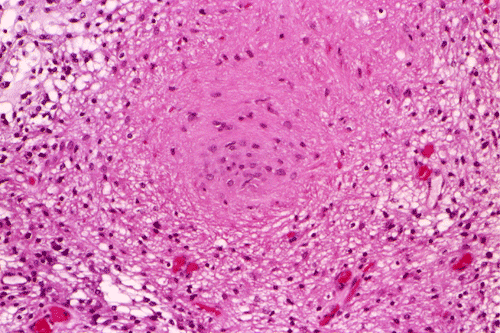

These photos were obtained from the formalin fixed paraffin embedded sections.

Com401-2-Perm01.gif (145631 bytes) Com401-2-Perm02.gif (137202 bytes) Com401-2-Perm03.gif (136949 bytes) Com401-2-Perm05.gif (135940 bytes) Com401-2-Perm06.gif (133968 bytes) Com401-2-Perm07.gif (137355 bytes)